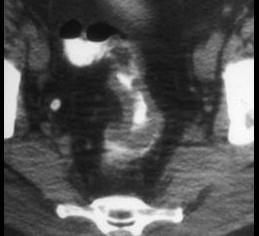

问题 男,53岁,便秘、血便,大便变细,CT如图,应考虑为 ( )

选项 A、慢性溃疡性结肠炎 B、直肠淋巴瘤 C、直肠结核 D、溃疡型直肠癌 E、肠crohn病

答案 D